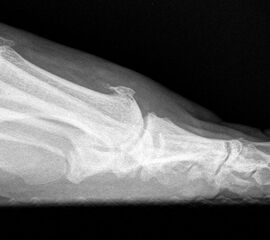

Klinisch zeigt sich stadienabhängig eine schmerzhafte Bewegungseinschränkung mit zunehmender Steifigkeit des Großzehengrundgelenkes. Vor allem die Einschränkung der Dorsalextension wird von den Patienten oft als unangenehm empfunden. Initial besteht eine bindegewebige Alteration im Gelenk, im weiteren Stadium treten Knorpeldegeneration und Begleitsynovialitis mit der Ausbildung von osteophytären Randanbauten auf. Klinische treten diese meist durch eine schmerzhafte dorsale Knochenkante in Erscheinung (Abbildung 1).

Im späten Stadium imponiert eine Gelenkblockierung durch freie Gelenkkörper. Während in den Anfangsstadien vor allem die dorsalen Anteile des Gelenks betroffen sind, betreffen die Veränderungen in den Fortgeschrittenen Stadien die gesamte Zirkumferenz einschließlich des Sesambeingleitlagers. Im Endstadium kommt es zu einer weitgehenden Ankylosierung des 1. Metatarsophalangealgelenks.